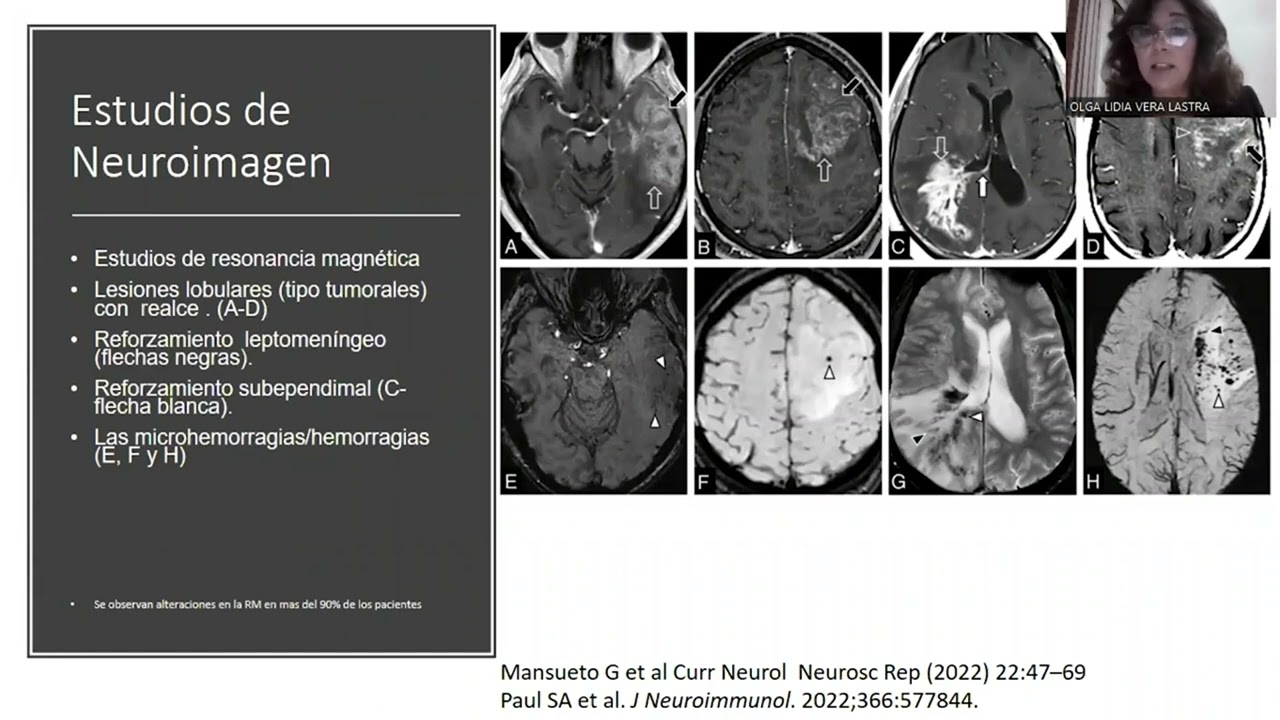

Vasculitis Primaria del Sistema Nervioso Central.

Dra. Olga Lidia Vera Lastra